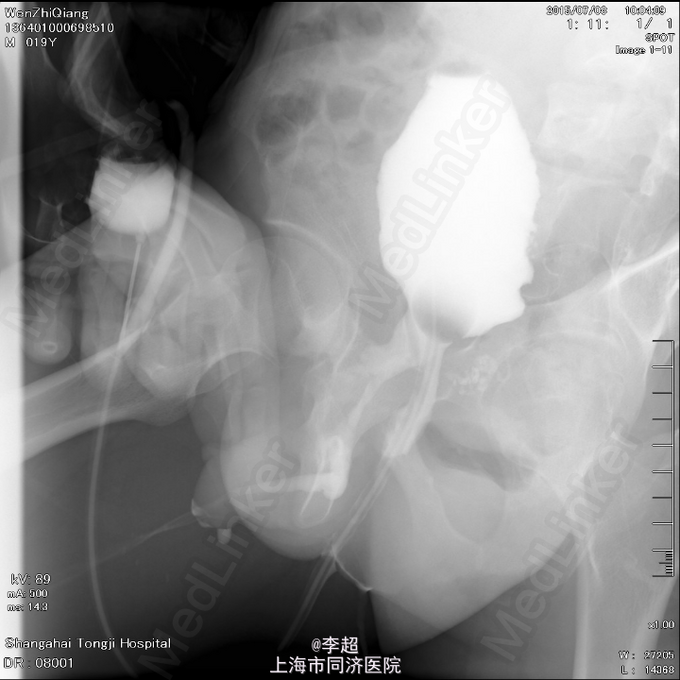

查体 辅查

患者尿道开口于阴囊下,会阴部,无法控尿,尿液自行流出 尿道造影仅显示假道,正常尿道仅存留阴茎短尿道,约5cm长

择期行耻骨下缘切除+阴囊皮瓣代尿道成形+尿道膀胱拖入术 手术过程:行会阴部倒Y形切口切口,切口包括会阴部尿道造口处,术中见阴茎部尿道存在尿道-阴茎皮肤瘘道,予切除瘘道。分离后尿道,探查见后尿道疤痕明显,并且于耻骨相连,局部粘连严重。考虑有假道存在可能,遂做耻骨上纵行切口4cm,探查膀胱发现距目前尿道口处1cm处前方存在另一内口,为盲道,盲端被变形耻骨完全遮挡。遂使用骨刀劈凿穿耻骨并切除耻骨下缘,凿通至膀胱盲道,将盲端断断显露,使用膀胱镜探查盲道,见盲端口膀胱肌肉括约功能较好,推断为真性尿道,使用左侧阴囊及大腿根部皮瓣约8cm*3cm大小,分离皮瓣下组织血管形成血管蒂,翻转皮瓣形成尿道,将皮瓣尿道近端拖入膀胱,与真性尿道膀胱黏膜处直针缝合。另将皮瓣尿道远端与阴茎部正常尿道粘膜缝合,留置F14号导尿管,假道处尿道予留置Foley14导尿管。